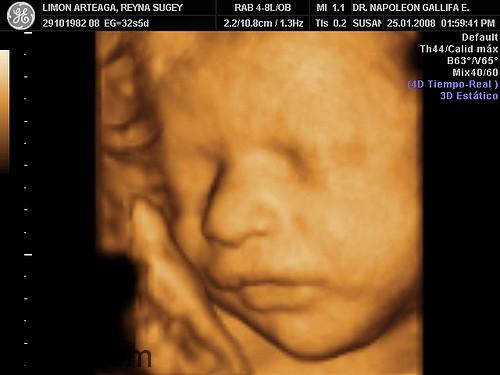

2. Siêu âm 4D

Kỹ thuật siêu âm 4D đã đưa vào công nghệ siêu âm một bước ngoặc hiện đại mới. Biến những tấm hình siêu âm đen trắng với những con số chưa rõ ràng thành những hình ảnh có màu sắc và chính xác. Siêu âm 4D ra đời trên nền tảng của kỹ thuật siêu âm 3D và 2D, vì thế mà siêu âm 4D có những điểm vượt trội hơn.

Siêu âm 4D là siêu âm 4 chiều (gồm 3 chiều không gian và 1 chiều thời gian). Máy siêu âm màu 4D của Medison được sử dụng trong siêu âm thai nhi, nhờ 3 chiều không gian và chiều thời gian giúp cho chúng ta quan sát được không gian 3 chiều của thai nhi cùng với những cử động ngộ nghĩnh đáng yêu của em bé trong bụng mẹ.

Siêu âm 4D-Hình thái thai nhi ngoài giúp chúng ta quan sát được hình thể bên ngoài, những cử động ngộ nghĩnh đáng yêu của thai nhi còn nhằm mục đích kiểm tra, phát hiện dị tật thai nhi sớm hay nói đúng hơn mục đích chính của siêu âm 4D-Hình thái thai nhi là để “Kiểm tra, phát hiện dị tật thai nhi sớm”. Giá tiền siêu âm còn tùy thuộc vào rất nhiều yếu tố và việc bạn lựa chọn siêu âm 2D, 3D hay 4D, tuy nhiên giá tiền chỉ tốn khoảng chừng từ 100.000đ đến 500.000đ một lần siêu âm.